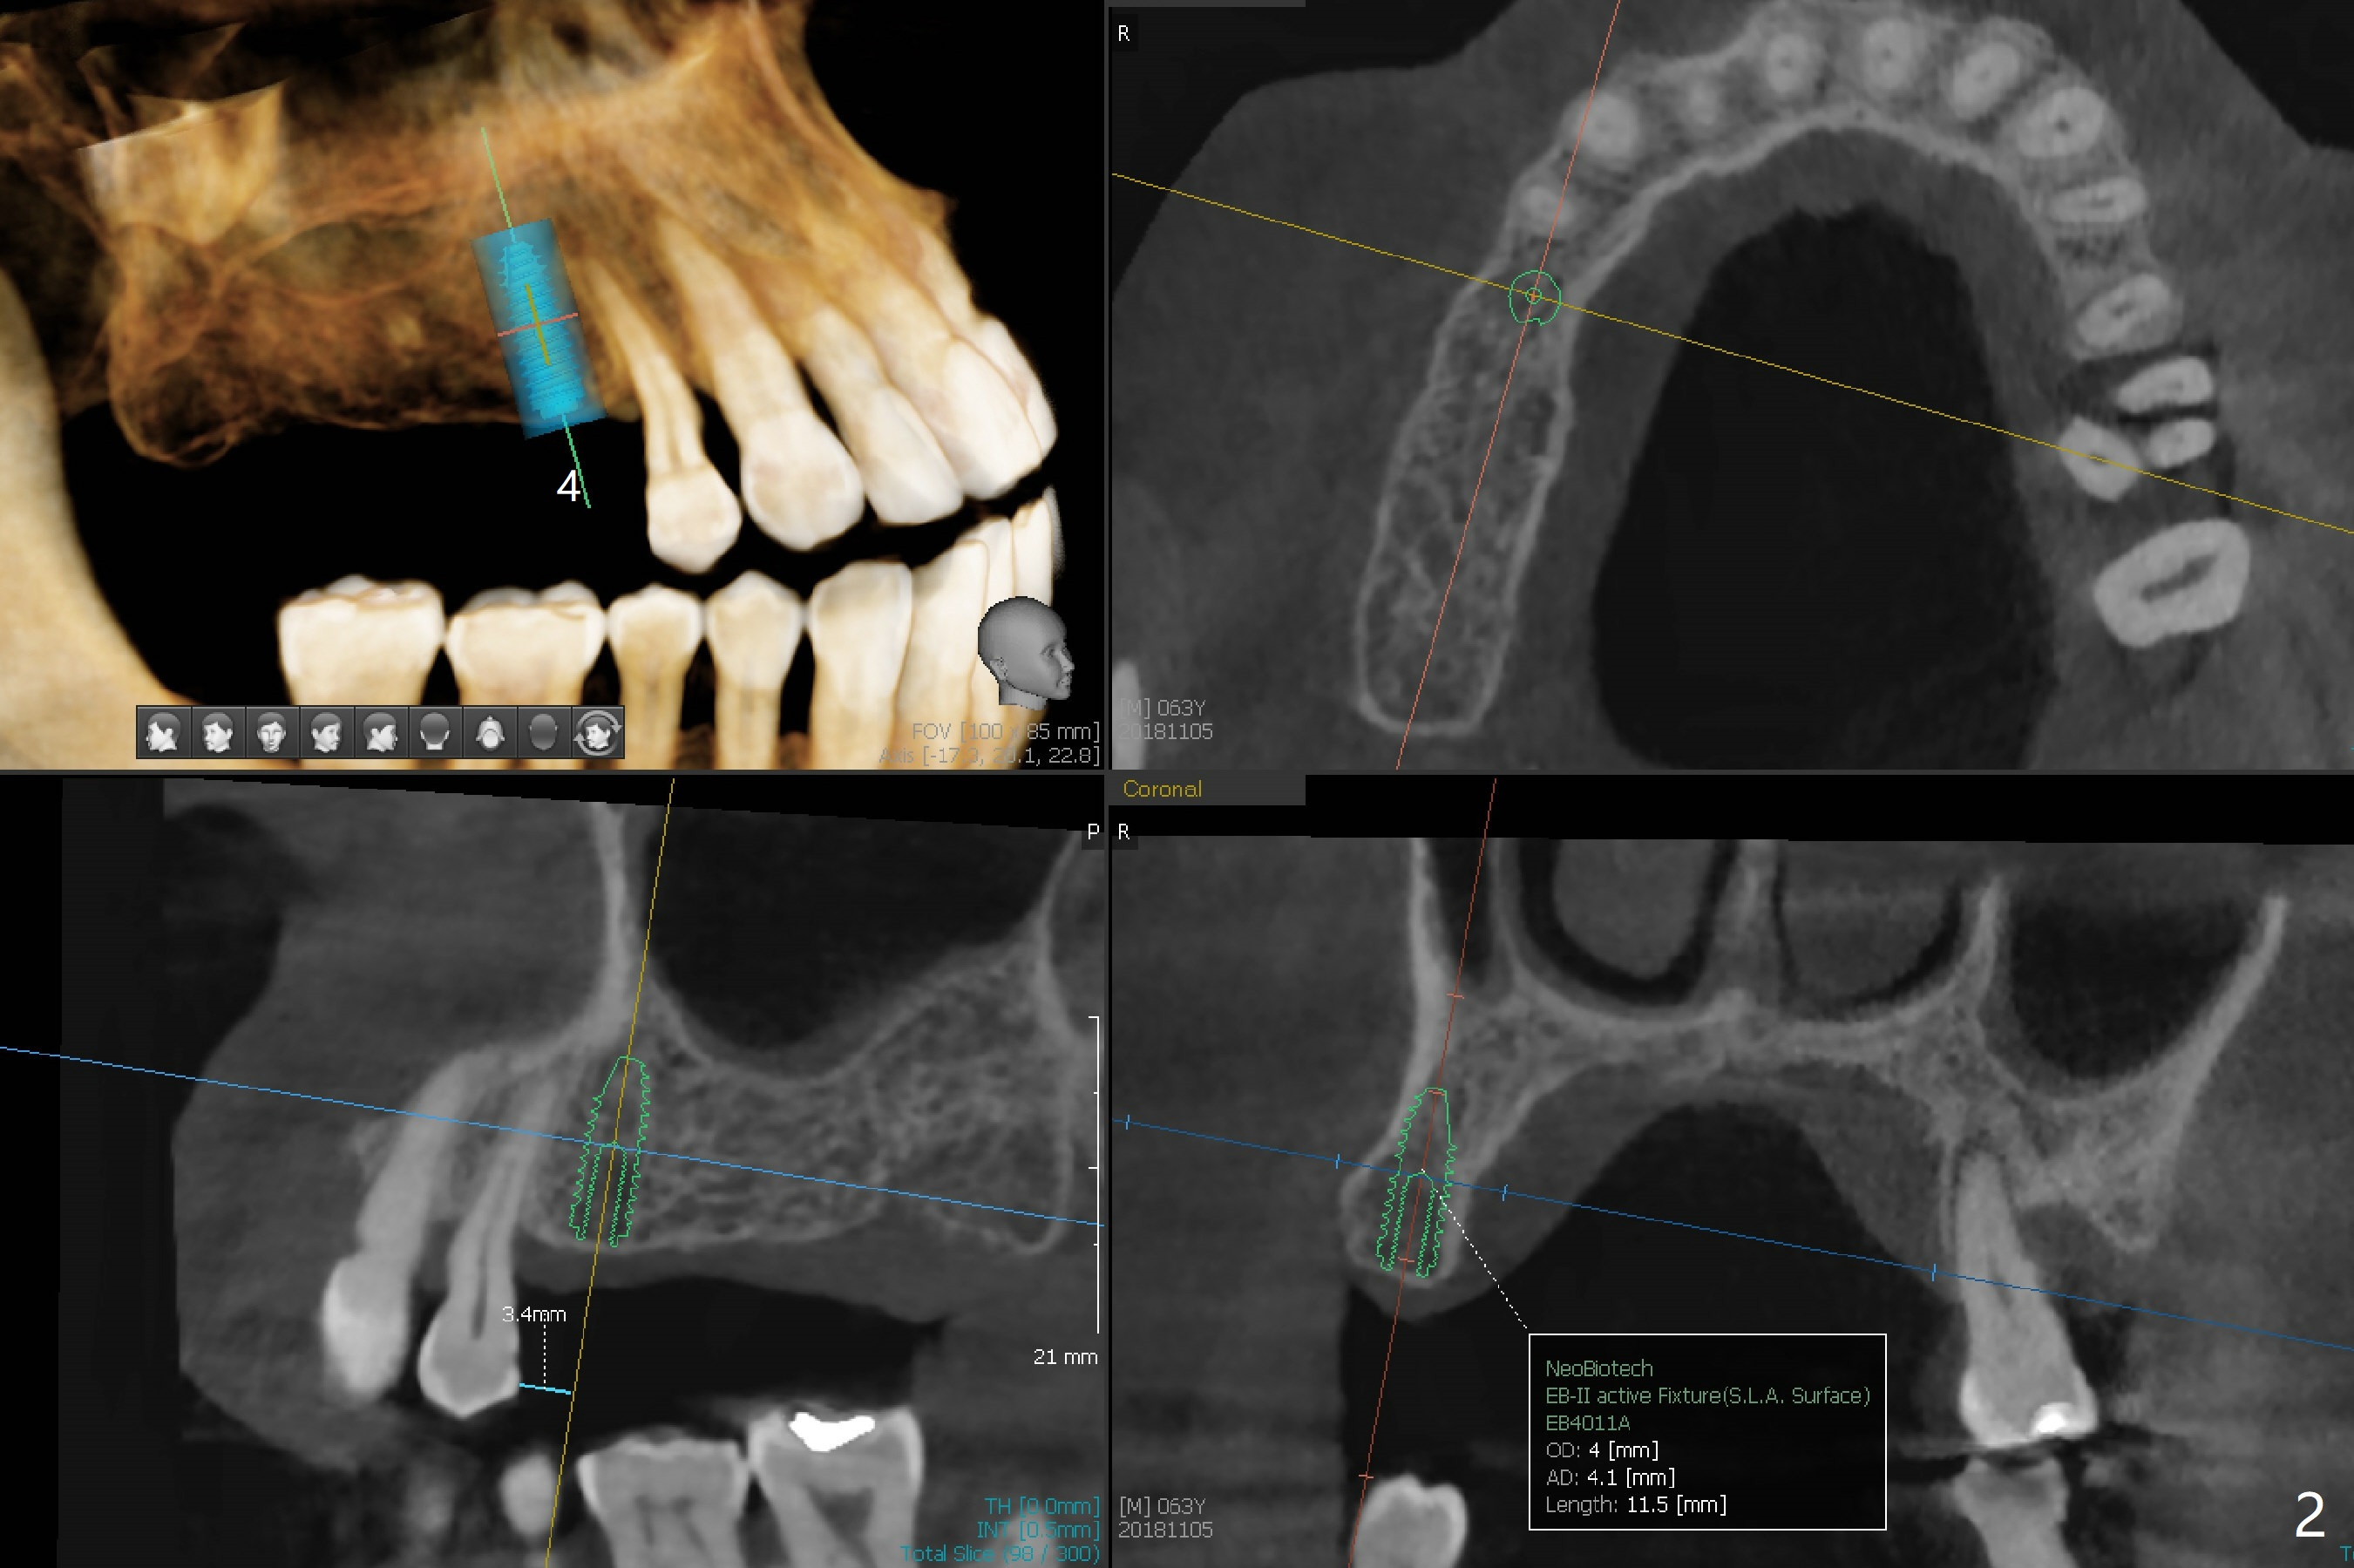

A 63-year-old man lives out of state and returns to office for scaling with chief complaint of occasional upper left pain (#14, Fig.1). After discussion, he agrees to have implant restoration in the upper right quadrant (#2-4). It appears that a 3-unit FPD is appropriate (Fig.2,3). When the teeth #14 and 19 fail, immediate implants will be placed (Fig.4-6).